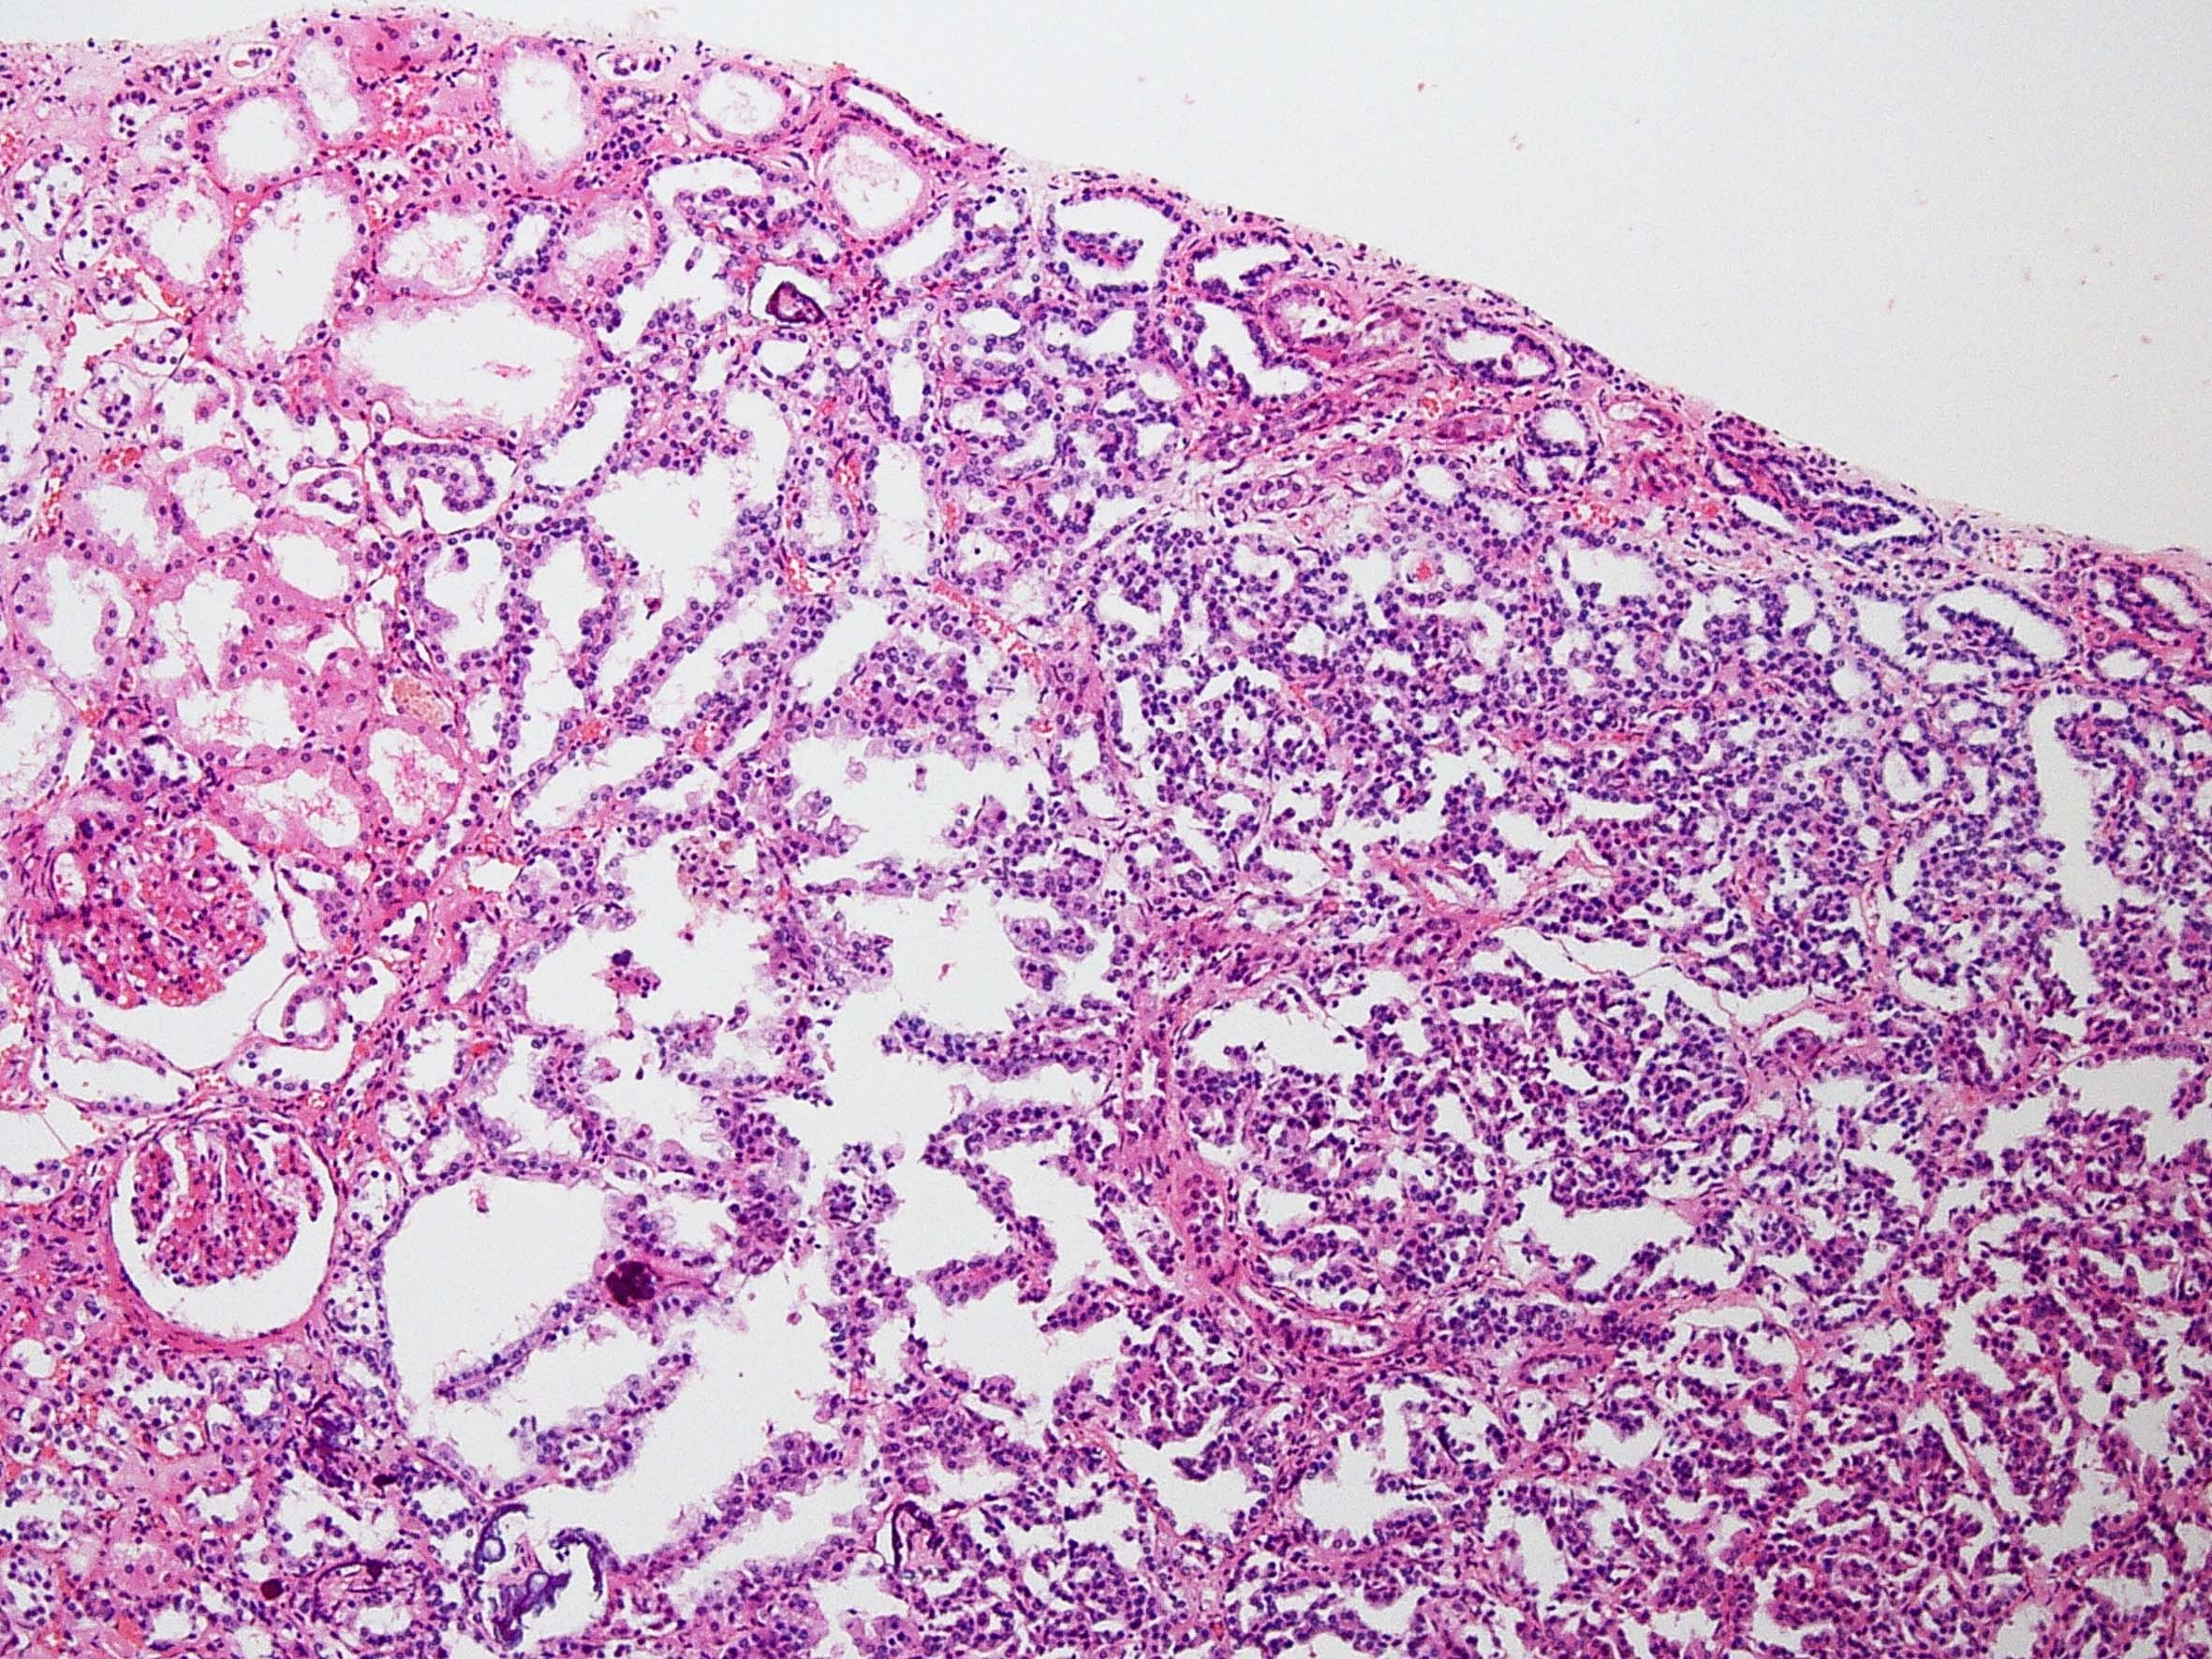

Case description (by case creator):

Papillary adenoma